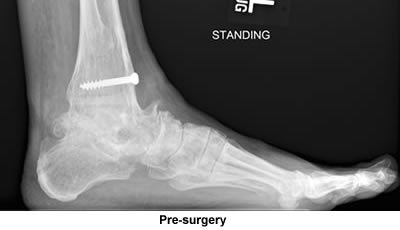

The orthopedic surgeon told me not to run again. When walking started to be painful too, the surgeon suggested a fusion of the Tibia and the Talus. The first surgery was unsuccessful but the second surgery was successful and it was great to have a pain free ankle.

I was all set to have the surgery done elsewhere on just one joint. Casually looking through the Cape Cod Times and spotting your ad for surgery on all sorts of foot problems and stating you were also available for consultation at your office in Bourne immediately convinced me to visit you as I did have some reservations about the surgery I was about to have. I figured that you would confirm that surgery, but that was not the case; you told me three joints were gone and needed fusions. You sent me a very convincing email and also fit me into your surgery schedule much sooner than normally would be expected because of your full workload. I just can't thank you enough for what your surgery has done for me.